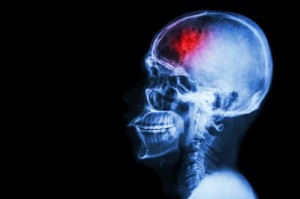

Пациенты с инсультом имеют высокий риск суицида

Новое исследование, проведенное шведскими учеными, обнаружило, что пациенты, пережившие инсульт, имеют вдвое больший риск совершения суицида по сравнению с людьми, не имевшим инсульта. Результаты данного исследования были опубликованы в журнале Neurology. Также исследователи отмечают, что вероятность попытки суицида среди данной группы является наиболее высокой в течение первых двух лет после инсульта.